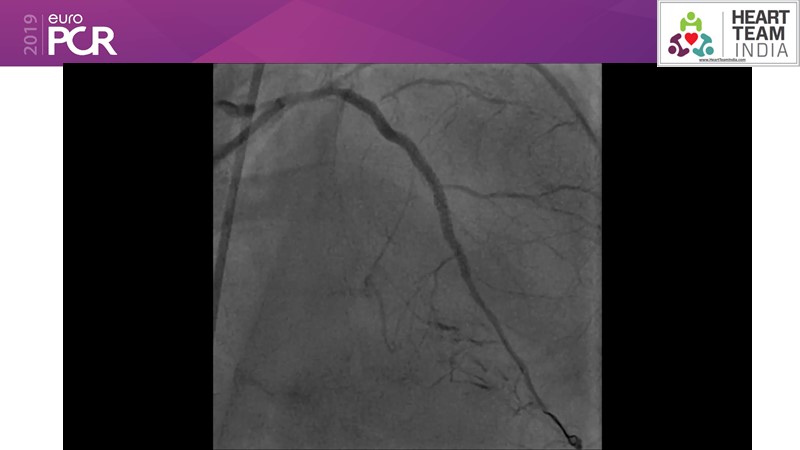

Ability to treat diabetic patients: DES + DCB strategy

Consult this session to get insights about the need for a dedicated drug eluting stent (DES), as well as the benefits of a DES+DCB strategy, for diabetes mellitus (DM) and acute MI (AMI) patients.

- To understand and discuss the need for a dedicated DES for diabetes mellitus (DM) and acute MI (AMI) patients

- To understand and learn benefits of DES+DCB strategy to provide uniform and homogenous drug delivery in patients with diabetes mellitus and acute MI